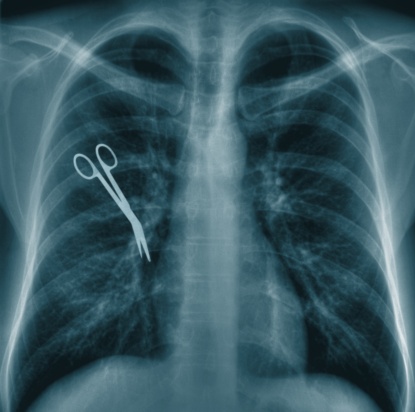

מתן שירותים רפואיים תוך סטייה מרמת הזהירות הסבירה וכאשר הסטייה גורמת נזק למטופל יוצרים את עוולת הרשלנות הרפואית. רשלנות זו יכולה לבוא לידי ביטוי בתהליכים פשוטים כמו רישום תרופה שאינה מתאימה, או בניתוחים מורכבים ואפילו גרימת מוות לחולה. רשלנות רפואית היא רק סוג אחד של רשלנות ותביעות אזרחיות בגין העוולה הזו משויכות אל דיני נזיקין. לפיכך, תקופת ההתיישנות החלה על תביעות רשלנות רפואית נגזרת גם היא מתוך יחסו של החוק אל דיני נזיקין.